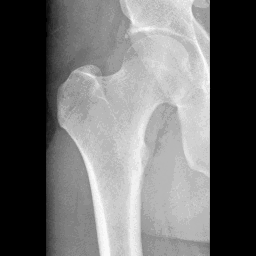

ScribblePrompt The main goal of the tool is to simplify the segmentation process of medical images, which is crucial in applications such as tumor detection and organ contouring. Instead of relying on a large amount of manually annotated data, the tool allows users to guide the model to optimize the segmentation results with a small amount of input (such as simple scribbles or points). This approach reduces the time and effort of medical experts in image annotation while ensuring the accuracy of segmentation.

Effect examples

![]() | ![]() | ![]() |